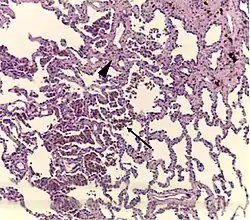

Histopathology of respiratory bronchiolitis: Smoker's macrophages (arrow); mild interstitial lymphocytic infiltrate and mild fibrosis (arrowhead)[2]

Histopathology of smoker's macrophages with anthracotic stippling, indicating the presence of both respiratory bronchiolitis and anthracosis.